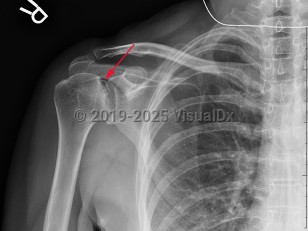

Grade / classification system: Cruess classification

- Stage 4 – flattening and collapse on x-ray